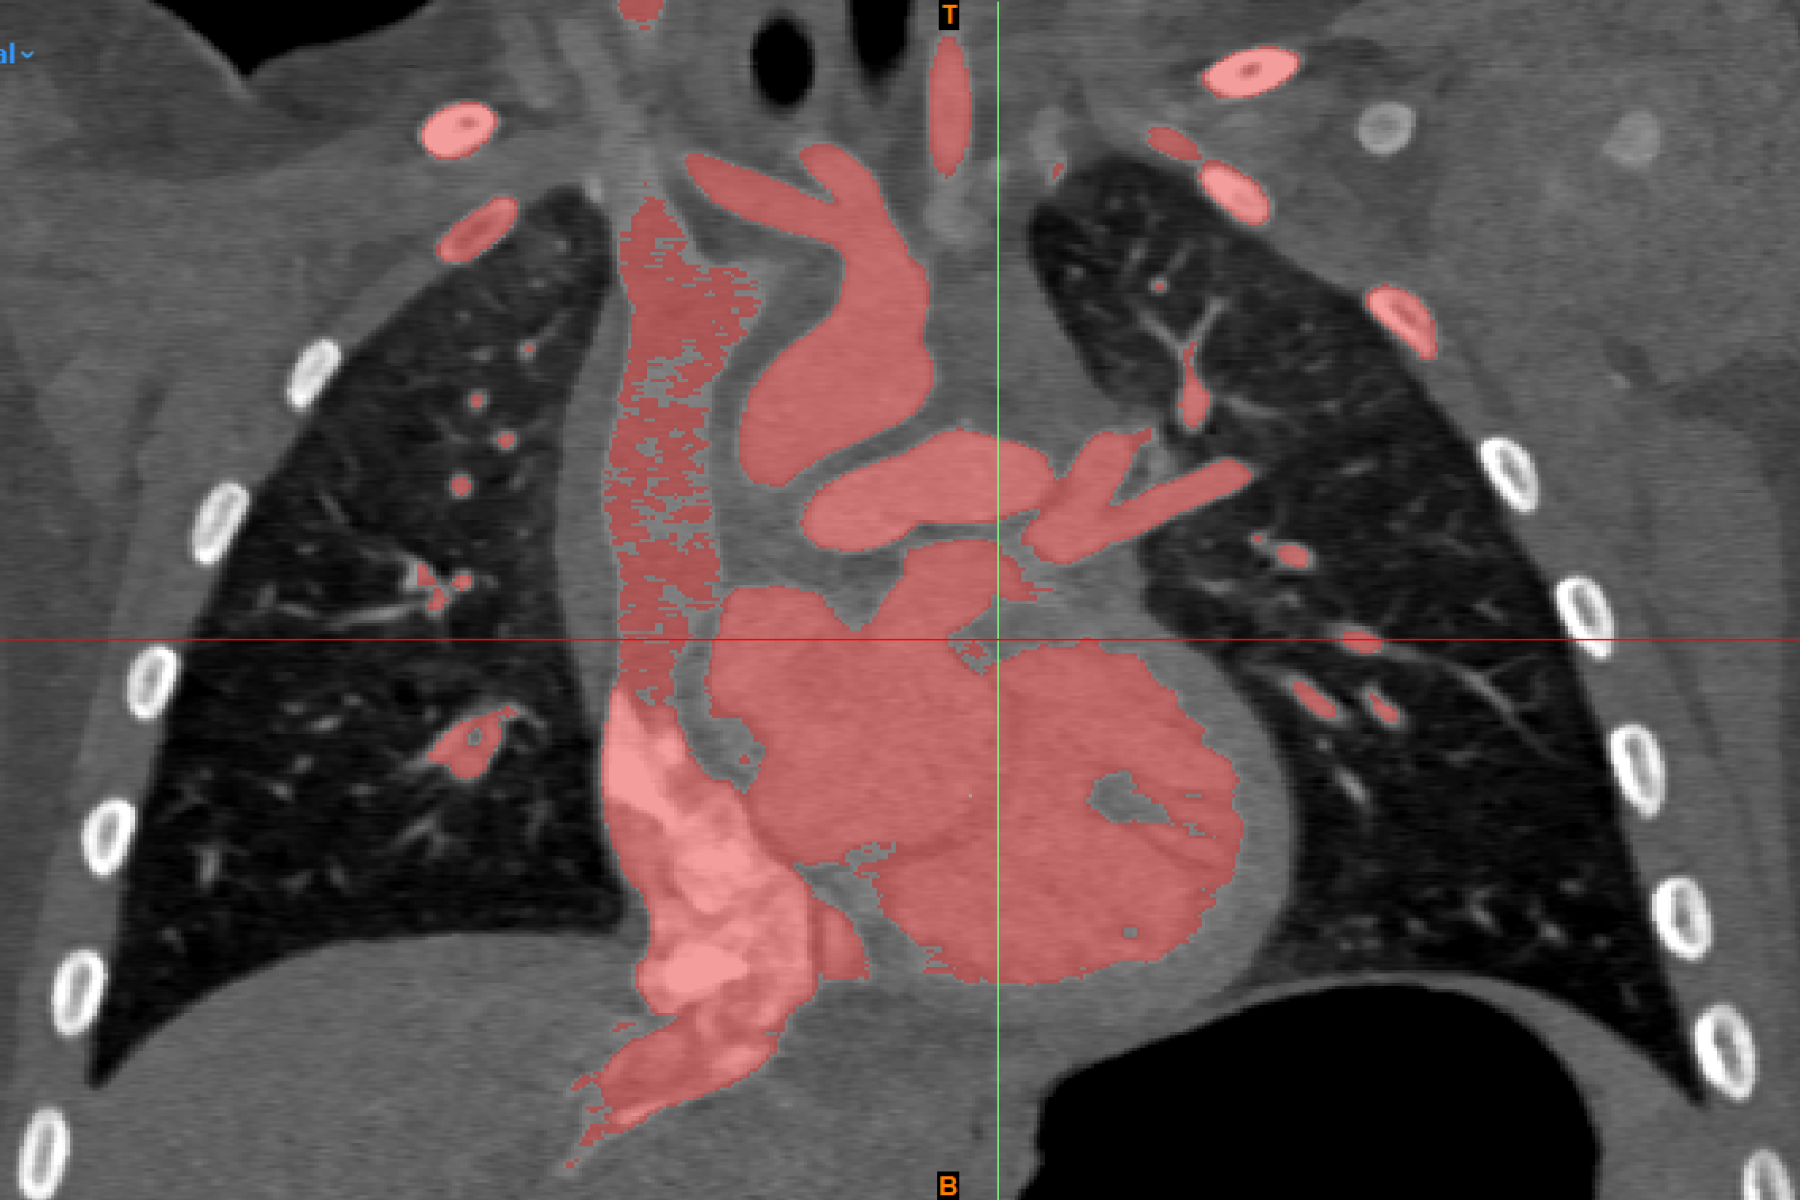

To develop this surgical training tool, the Digital Lab utilized established 3D modeling protocols. The virtual 3D model of the heart was developed with the abnormal anatomical features observed in patients with atrial septostomy, notably, the transposition of the great arteries which impacts the proper flow of oxygenated blood. The model was developed in consultation with a pediatric cardiologist using contrast-enhanced computed tomography scans obtained from infants with this condition. After the virtual model was approved, a physical model was fabricated following standard procedures established by the Digital Lab.

To ensure that the 3D printed heart was able to effectively replicate the elasticity and texture of cardiac tissue and provide a realistic experience to users, flexible and rubber-like materials were utilized during the printing process. Extended blood vessels were included to replicate the access points used by surgeons completing this procedure. A 5mm hole was created in the atrial septum to simulate the atrial septal defect (ASD). This 3D printed heart was then suspended within a simulator developed using Computer-Aided Design (CAD) software. This simulator provides access points that accommodate training for different procedural approaches to ensure that the model is generalizable.